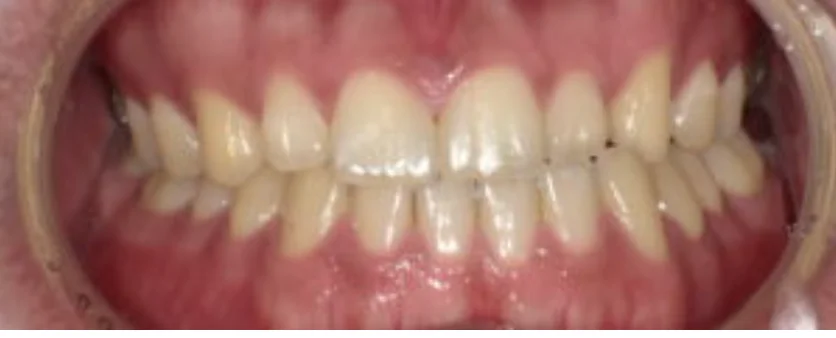

Before

After

セラミック治療により冷水痛と審美障害を改善(20代男性)

2回 / 総額50,000円リスク・副作用:セラミックの硬度は天然歯と同程度なので咬む力が強い方、夜間歯ぎしりをされる癖がある方はかけたり割れたりする事がある為、それらに対しても対応していく必要がある。